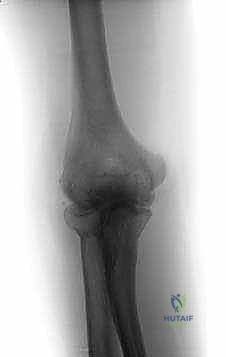

- التصوير بالأشعة السينية (X-rays): الفحص الأساسي الذي يُظهر تضيق المسافة المفصلية (دليل على تآكل الغضروف)، ووجود النتوءات العظمية، والأجسام السائبة الكبيرة.

- الأشعة المقطعية ثلاثية الأبعاد (3D CT Scan): أداة حاسمة ومفضلة لدى د. هطيف قبل أي تدخل جراحي. توفر الأشعة المقطعية خريطة ثلاثية الأبعاد دقيقة لموقع وحجم النتوءات العظمية والأجسام السائبة، مما يساعد في التخطيط الجراحي المسبق لضمان إزالتها بالكامل أثناء التنظير.